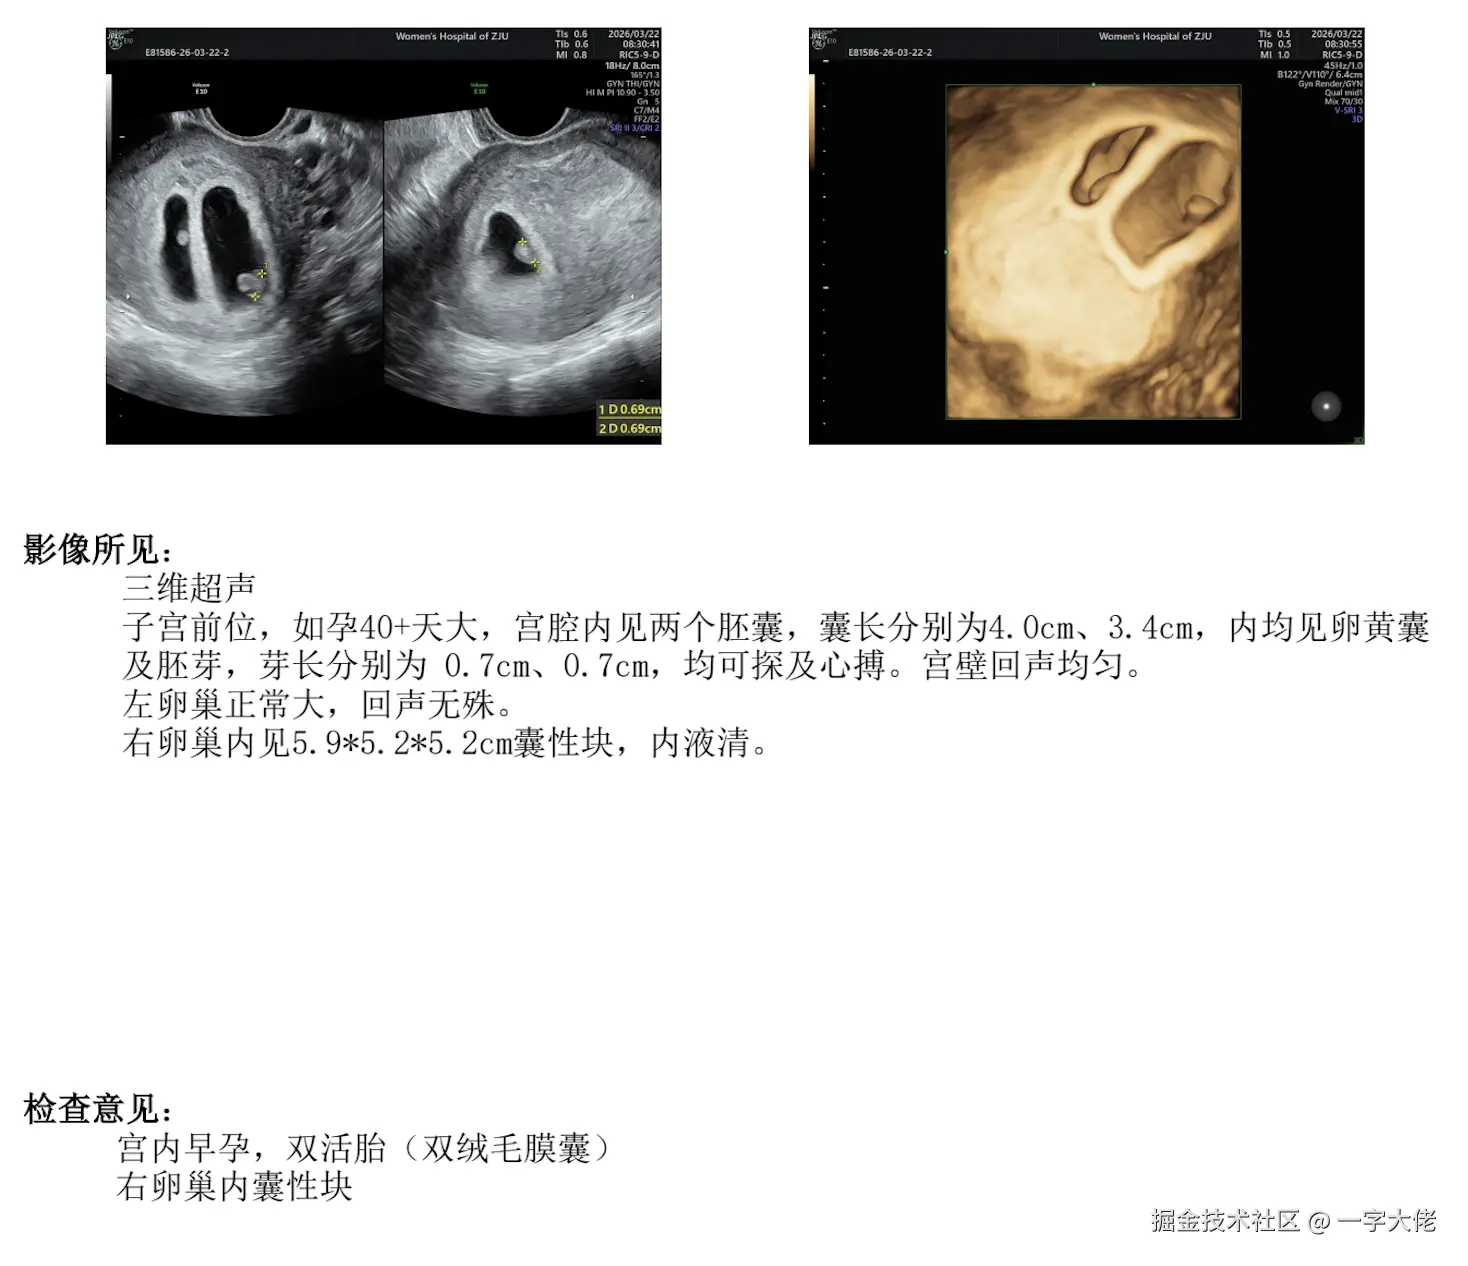

jym,又紧张又焦虑又开心。我滴老天爷。